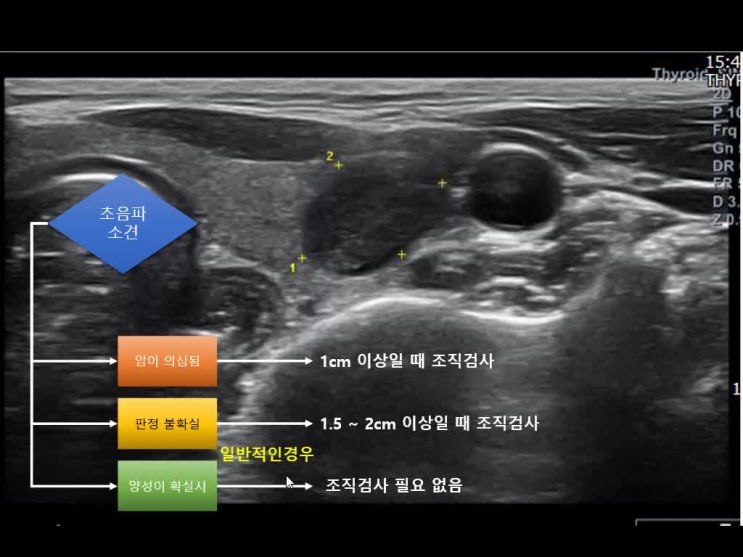

- 종합적으로 오른쪽은 암, 왼쪽은 암은 아니지만 깨끗하지 않은 상태라고 알려주셨다.갑상선 초음파 검사에서 둘 다 암이 의심됐지만 역시 확실한 것은 열어봐야 알 것 같아.